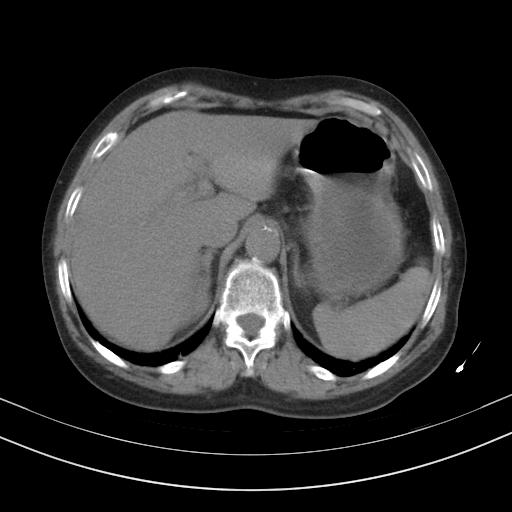

老年女性,嗜睡3天,意识模糊。轻咳,无发热。

1)两肺感染性病变;建议抗炎治疗后复查。2)纵隔淋巴结肿大。3)左侧胸腔积液。

1)先考虑两肺感染性病变;建议抗炎治疗后复查。

2)纵隔淋巴结肿大。

3)左侧胸腔积液。